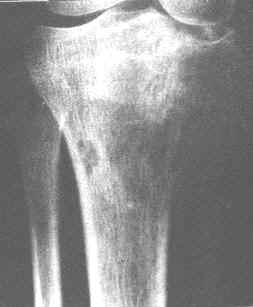

胫骨骨肉瘤(溶骨型)。胫骨上端偏内侧骨松质虫蚀状骨破坏,局部骨皮质消失。

6.分化原始的肉瘤新骨生长很少,骨质破坏显著,成为以破骨为主的溶骨型骨肉瘤,其恶性程度一般较高,生长较迅速。实际上,多数病例为两者的混合型